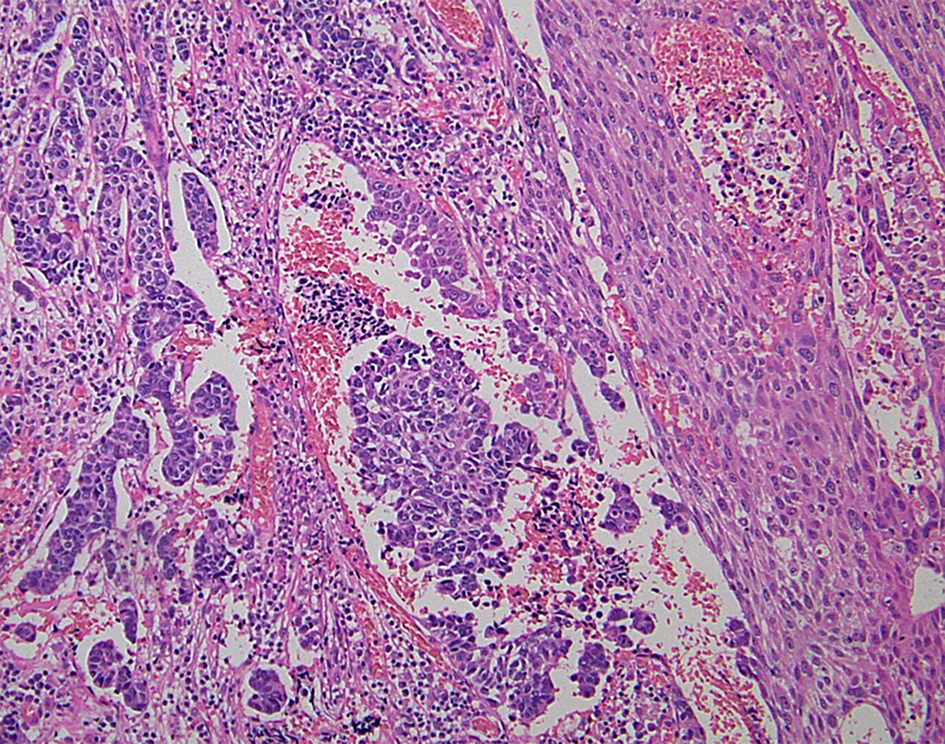

Most of the NENs arising from the esophagus are NECs, and NETs are rare (Hoang et al., 2002). Esophageal NENs commonly occur in the mid to lower segments of the esophagus (Hoang et al., 2002; Yun et al., 2007). Esophageal NETs appear to arise in two ways: as an incidental finding in association with Barrett esophagus and adenocarcinoma or as a single large polypoid or nodular tumor (Hoang et al., 2002). Upon immunohistochemistry, esophageal NETs are observed to strongly express chromogranin and synaptophysin, and some additionally express serotonin, glucagon, or pancreatic polypeptide (Hoang et al., 2002). Esophageal small-cell carcinoma has similar histological features to lung small-cell carcinoma (Yun et al., 2007). The majority of pulmonary small-cell carcinomas express thyroid transcription factor-1 (TTF-1) (Ordonez, 2000). Similarly, esophageal small-cell carcinomas also often express TTF-1 (33–71%) (Yamamoto et al., 2003; Yun et al., 2007). Combined tumors of NEC and squamous cell carcinoma have been reported (Figure 4) (Yamamoto et al., 2003). Esophageal NECs coexisting with Barrett mucosa or Barrett's esophageal adenocarcinoma have been also reported, as have NETs (Bibeau et al., 2008). Some cases of esophageal NENs show endocrine cell hyperplasia in the Barrett mucosa, as well as invasive adenocarcinoma (Hoang et al., 2002). The presence of endocrine cell hyperplasia in Barrett mucosa and adenocarcinomas supports the hypothesis that esophageal NENs, Barrett mucosa, and adenocarcinomas arise from a common stem cell (Hoang et al., 2002).

Figure 4

Combined tumors of neuroendocrine carcinoma (NEC) (left) and squamous cell carcinoma (right) (H and E stain).